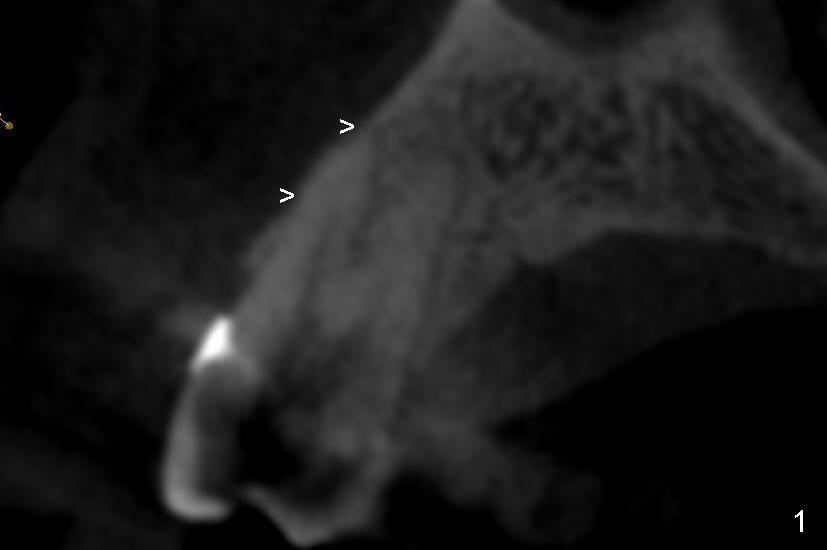

It is known that that buccal wall (apical) of anterior teeth including bicuspids is thin (Fig.1 between arrowheads). Fig.1 is a CT coronal section of an upper first bicuspid, whereas Fig.2 is a diagram showing after extraction. We are going to show how immediate implantation is to push the septum buccally (arrow) to close the buccal apical defect.